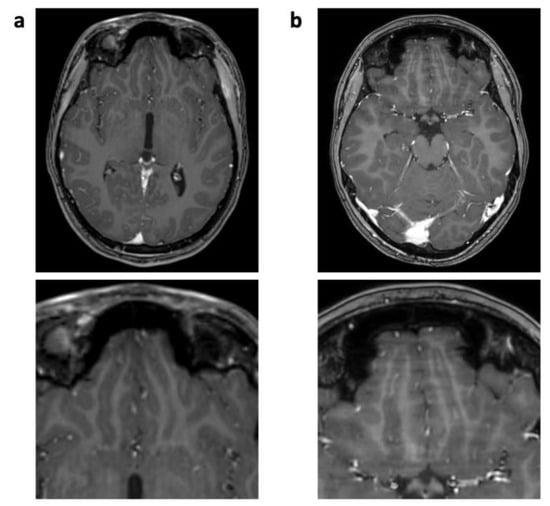

The “Wax-layer” artifact presented as patchy inhomogeneous blurring of brain structure mainly in post-contrast CS 3D T1 TFE (Figure 5).

Figure 5.

Enhanced 3D T1 TFE images of a 12-year-old male patient with non-germinomatous germ cell tumor (not shown). Wax-layer artifact presenting as patchy to blurred signal inhomogeneity in the pons and cerebellum in CS (b); not present in previous SENSE study (a).